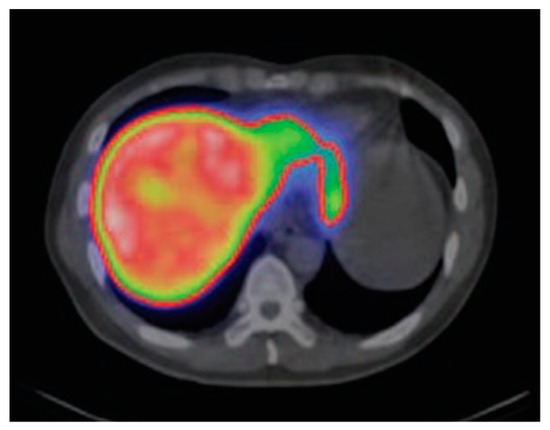

- Matesan, M.M.; Bowen, S.R.; Chapman, T.R.; Miyaoka, R.S.; Velez, J.W.; Wanner, M.F.; Nyflot, M.J.; Apisarnthanarax, S.; Vesselle, H.J. Assessment of functional liver reserve: Old and new in 99mTc-sulfur colloid scintigraphy. Nucl. Med. Commun. 2017, 38, 577–586. [Google Scholar] [CrossRef]

- Kumar, B.; Miller, T.R.; Siegel, B.A.; Mathias, C.J.; Markham, J.; Ehrhardt, G.J.; Welch, M.J. Positron tomographic imaging of the liver: 68Ga iron hydroxide colloid. Am. J. Roentgenol. 1981, 136, 685–690. [Google Scholar] [CrossRef]